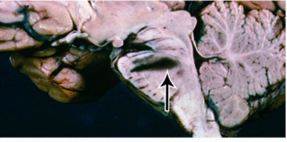

What does this image show?

Duret hemorrhage

As the uncus and brainstem are pushed downward, penetrating vessels become stretched and break. This leads to hemorrhages in the upper pons, Duret hemorrhages, that can be fatal.